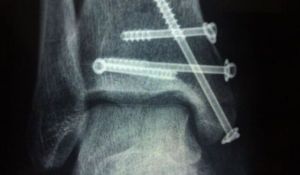

②截骨術適用於明顯的膝內、外翻和骨折明顯成角畸形癒合者,通過截骨可以減少骨內壓力,矯正重力線,並使比較完整的關節面承擔更多的體重負荷。

④關節融合術適用於單發的下肢負重關節,關節破壞嚴重而又比較年輕需要從事行走或站立工作的患者。

⑤關節成形術適用於疼痛嚴重,關節破壞嚴重的老年人人工關節置換術效果比較可靠如髖關節中心性脫位可致髖臼底部骨折或股骨頭軟骨骨折,破壞了髖關節的完整性,癒合後形成創傷性關節炎,或外傷性股骨頭缺血性壞死,若不採用全髖關節置換術,必將引起關節疼痛和功能障礙